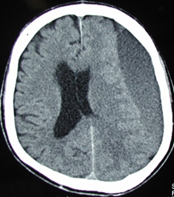

下の頭部CT画像は、歩きにくくなったという訴えで受診された高齢の男性で、左側(図の右側)の脳表に出血が貯まって脳が左から右に強く圧迫されています。頭部外傷から1~2か月経って発症する慢性硬膜下血腫という病気です。患者さんは1か月ほど前に転倒したとのことでした。

このように、受傷後2か月位までは後遺症に注意する必要があります。

慢性硬膜下血腫は、局所麻酔下の穿頭術で血腫を洗い流すと後遺症なく治癒しますので、心配な症状があったら頭部CT検査を受けることが大切です。